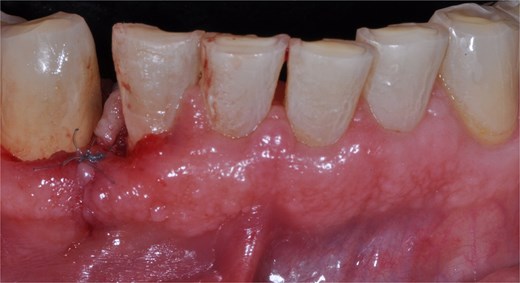

A 68-year-old male patient with no pathological history and healthy periodontium visited the dental clinic with the following complaint: ‘I have a lump on my gum that I bite when chewing.’ Intraoral examination revealed a mucogingival tissue growth on the attached gum, which was firm, oval, fibrous, smooth, and without signs of active ulceration, measuring ~1.1 × 1.0 cm. The lesion originated at the base of the papilla and part of the adjacent masticatory mucosa, presenting a pedunculated base that extended to the interproximal region of teeth 43 and 42, with erythematous coloration and whitish areas (Fig. 1a and b). The patient reported difficulty chewing, with no pain or history of trauma or surgery in the area. A digital periapical radiograph was performed to rule out periodontal or infectious pathology at the bone level.

Clinical image of mucogingival tissue growth in the attached gingiva, with a firm, oval, fibrous, smooth appearance and no signs of active ulceration. (a) Lateral view. (b) Frontal view.